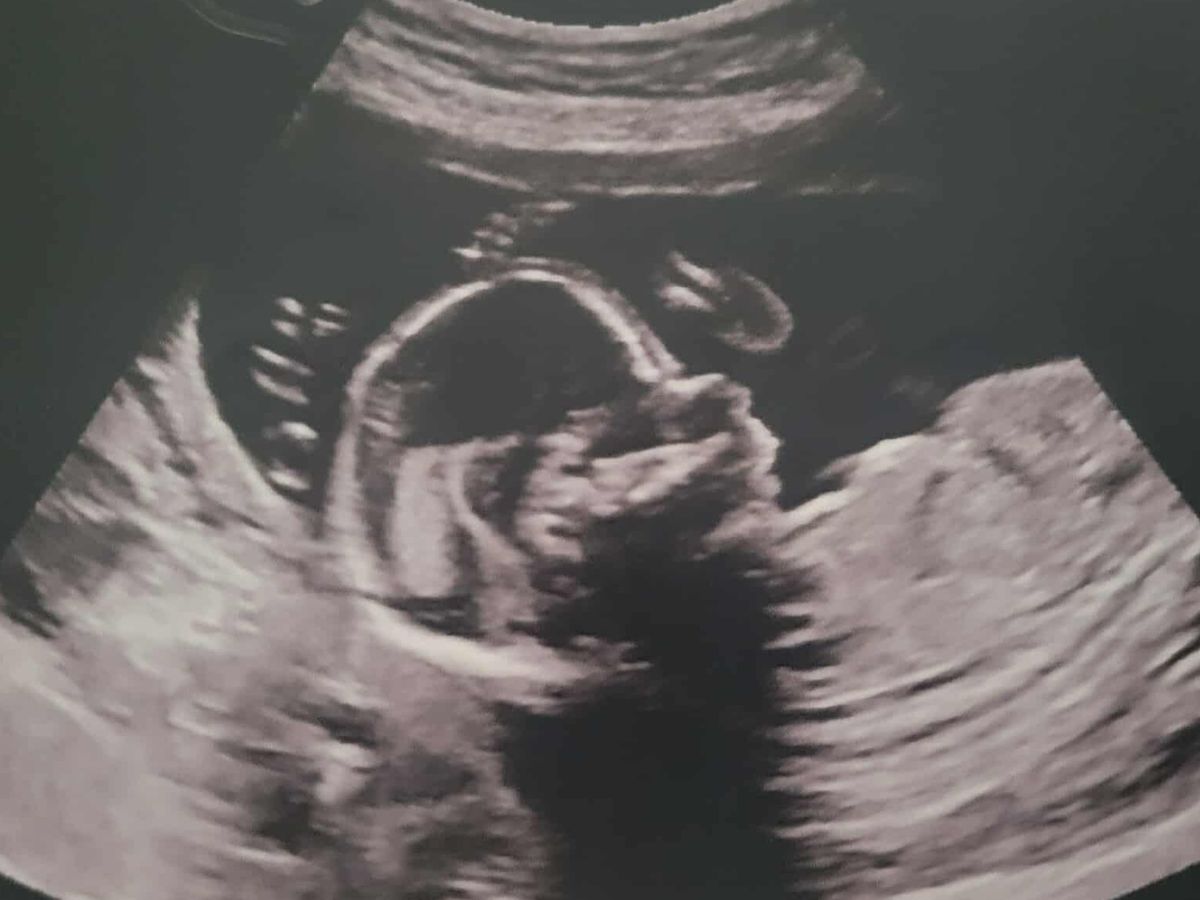

Hello, our names are Colleen and Jonathan King. We are reaching out for help with the journey of our baby girl, Oliviah. What began with the excitement of expecting another blessing from the Lord, with the silly gender mishap (as some of you know), and cute little outfits and bows, has turned to feelings of heartbrokenness, powerlessness, and shattered disbelief. Yet, through all of this, we remain hopeful, knowing that God has a hand in all of it. Following my 19-week ultrasound, we received the devastating news that Oliviah has been diagnosed with a L4 Myelomeningocele, a form of spina bifida. In Oliviah's case, the defect is low on her back, at the lumbar region, which is a good thing. She also shows the "banana and lemon signs," which is due to an elongated cerebellum, which is a sign of the Chiari II malformation, which means her brainstem is being pulled down into her spinal canal at the C2-C3 region. Her head circumference is also below percentile, caused by the Chiari II malformation.